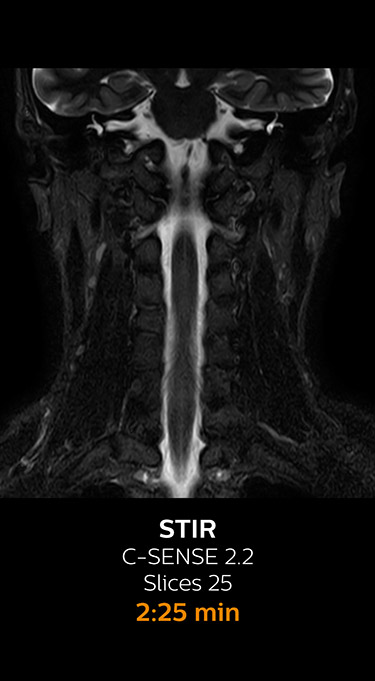

With Compressed SENSE, the scan time for the routine cervical spine examination at KNC was reduced from 13:11 to 9:52 minutes, which corresponds to 25% reduction.

MRI examination of the cervical spine with Compressed SENSE

Ingenia 3.0T CX

Scan time 9:52 min. (was 13:11 min. without Compressed SENSE)